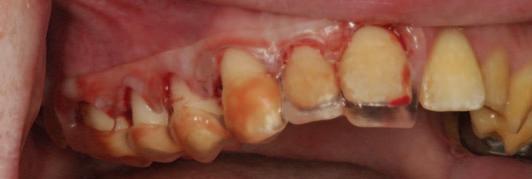

A unilateral sagittal split osteotomy was performed using piezosurgery to protect the nerve. The alveolar nerve, extending from the apical region of the left first and second molars to the mental foramen, was uncovered, and a meticulous dissection was performed to release it from the canal. Notably, rigid paste debris was observed in proximity to and within the nerve canal. The nerve exhibited signs of swelling and was surrounded by granulation tissue (Figures 4 and 5 ).

FIGURE 5: The root canal filling material being removed from the canal.